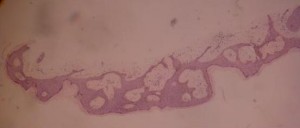

B. Reticulate (or adenoidal)

The epidermis is characterised by a thin strand of basaloid cells which extend from the follicular keratinocytes and intermingle with each other {Wade, 1979}. This type often displays focal areas of hyperkeratosis, areas where pseudocysts and horn cysts are to be found{Kirkham, 1997}.

It has been postulated that this type of KS has a close relationship with solar (senile) lentigo {Mehregan, 1975}(see causal factors).